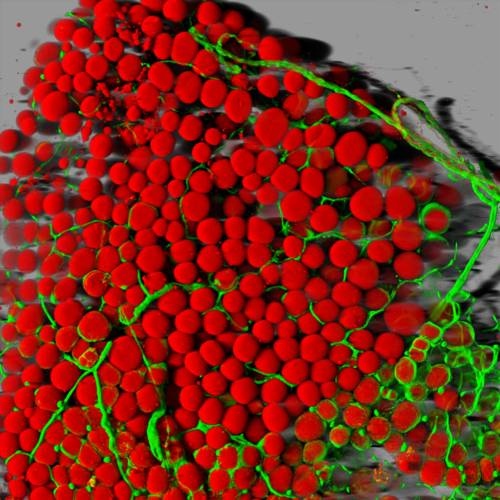

Células grasas de ratón (en rojo) aparecen rodeadas por una red de vasos sanguíneos (verde). (Imagen: Daniela Malide, National Heart, Lung, and Blood Institute, National Institutes of Health)